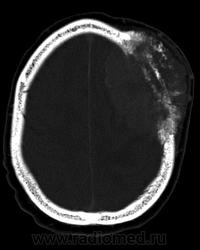

Фронтальная менингиома с гиперостозом и лизисом костной ткани.